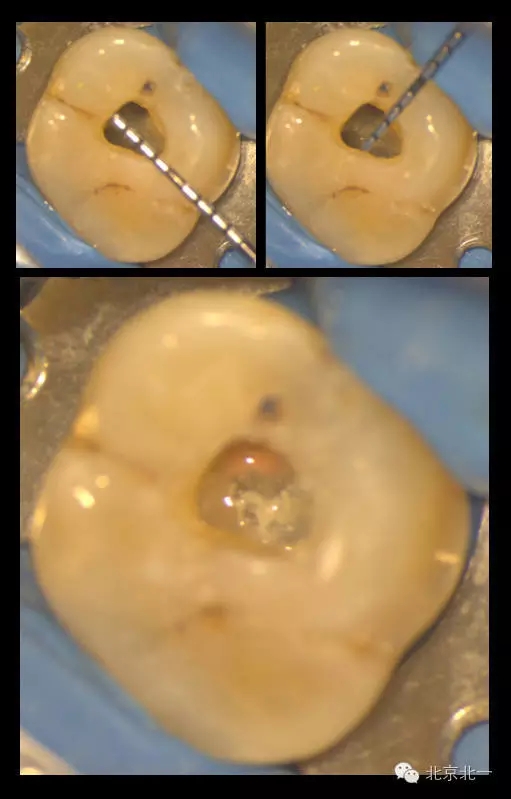

在我們看來,微創(chuàng)的入路設(shè)計(jì)是需要條件限制的。首要條件就是在入路開放后醫(yī)師能明確牙齒內(nèi)根管的分布與走行。醫(yī)師或者在術(shù)前通過CBCT明確根管解剖行程,或者能夠從開髓入口處檢視到髓底的全部區(qū)域以防遺漏根管。

下圖是我們研究生小苑的課題,在顯微CT的輔助下,借助牙面標(biāo)記點(diǎn)進(jìn)行髓腔入路的設(shè)計(jì):根據(jù)CT數(shù)據(jù)建立的根管模型,將每個(gè)根管的延長線投影至牙冠表面,連接各表面投影點(diǎn)后即為開髓的通道。這樣的開髓入路下,既暴露出了所有根管口,從不同的視角方向下也能看到完整的髓底解剖。